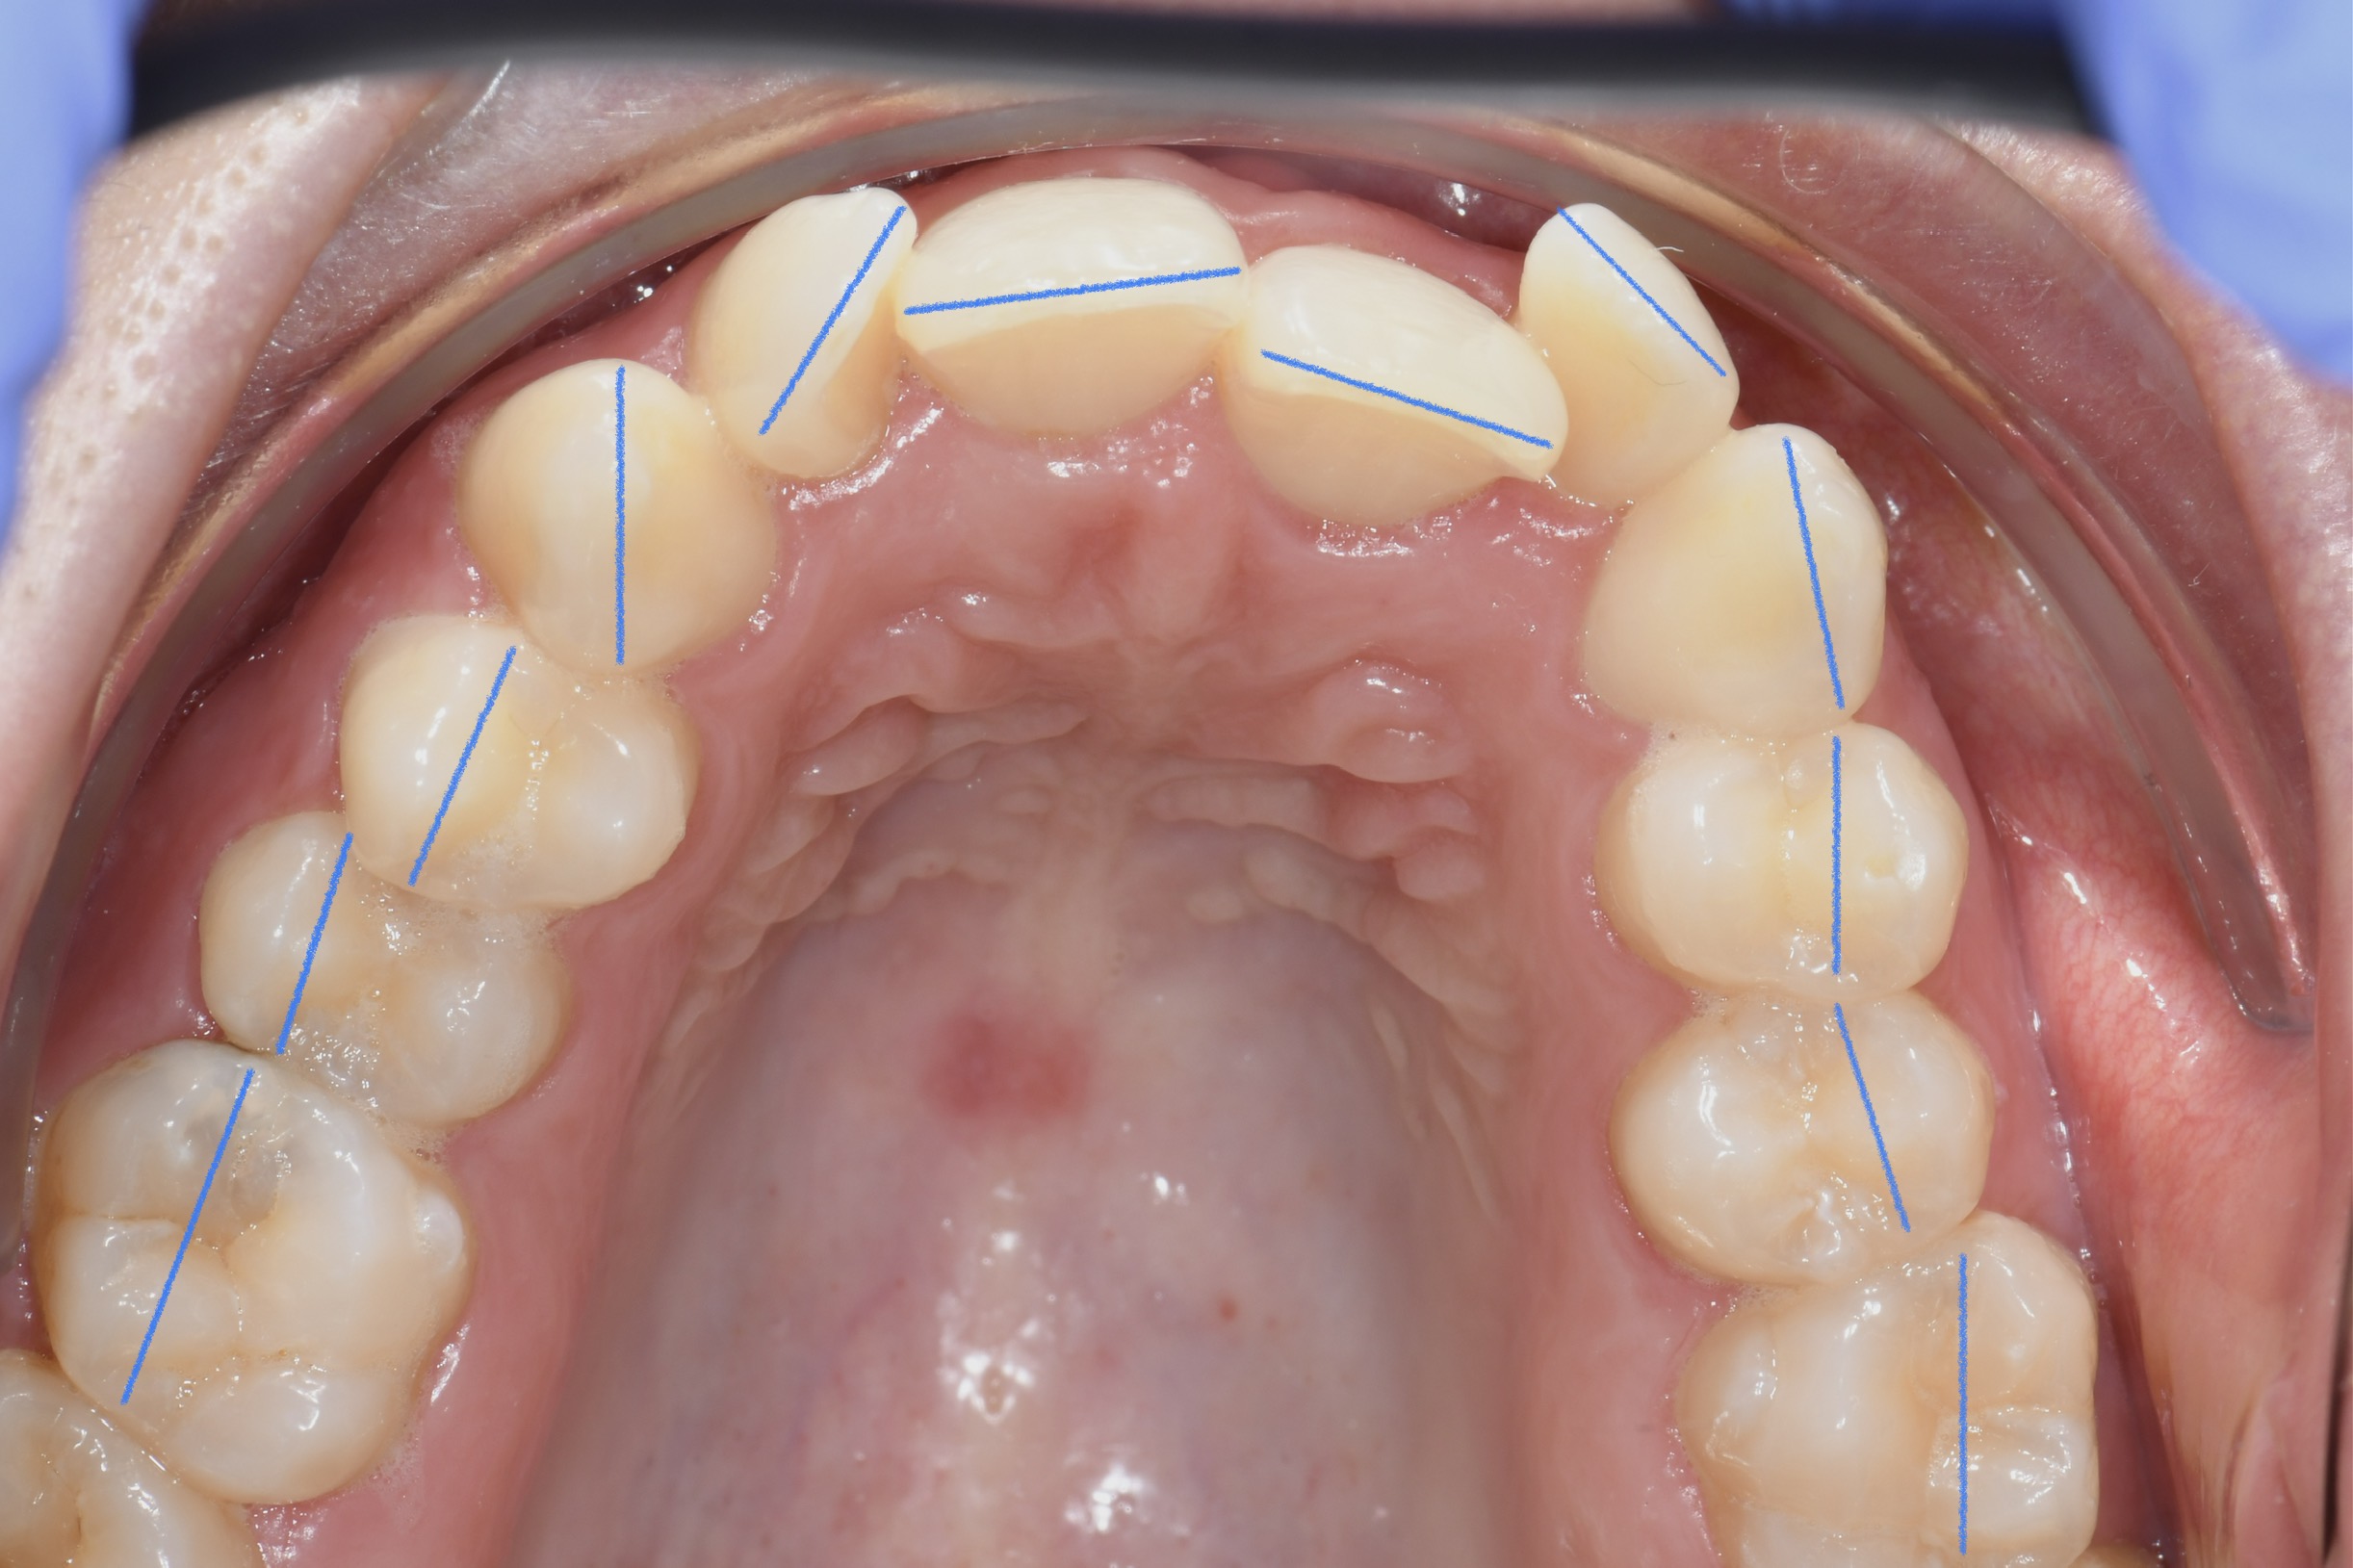

Az elmúlt évekből rengeteg szakmai referenciát tudnánk bemutatni, amelyek különböző fogszabályozási problémákat oldottak meg. Válogatva a több száz esetből, ezen az oldalon olyan képeket, információkat igyekeztünk bemutatni, amelyeknek a segítségével a jövőbeni pácienseinknek azt tudjuk üzenni: A Te fogsorod is lehet gyönyörű!

(Képeket a Pácienseink külön írásos beleegyezésével mutatjuk be!)